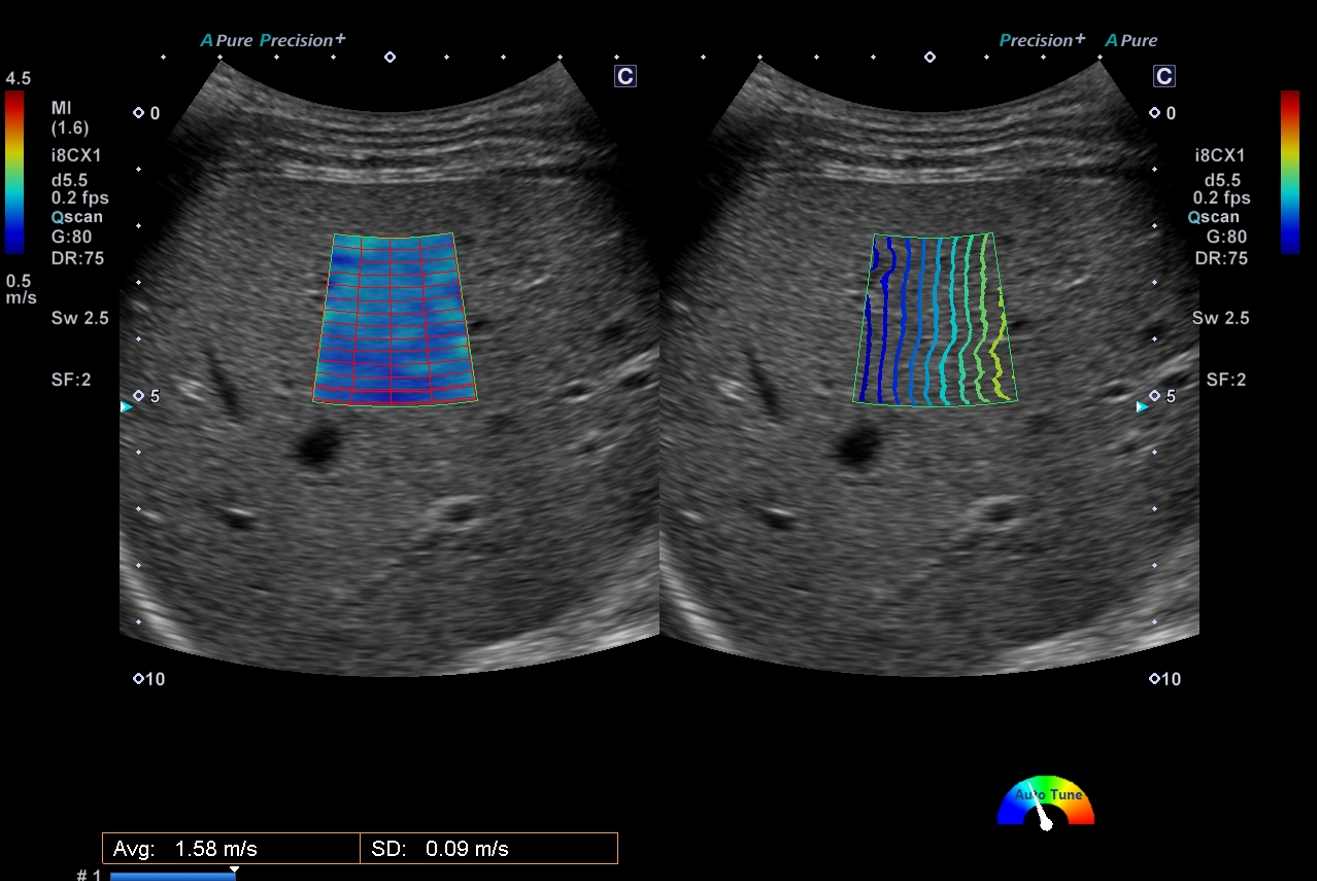

近年肝臓の硬さをエコーで評価可能となりました。せん断波の伝播速度を測定し、組織の硬さを数値やカラーマップで表示できます。せん断波の伝搬する時間を等高線表示するPropagation表示で、せん断波の伝わり方を視覚的に確認できます。

慢性肝炎や肝硬変の程度の評価が可能となります。